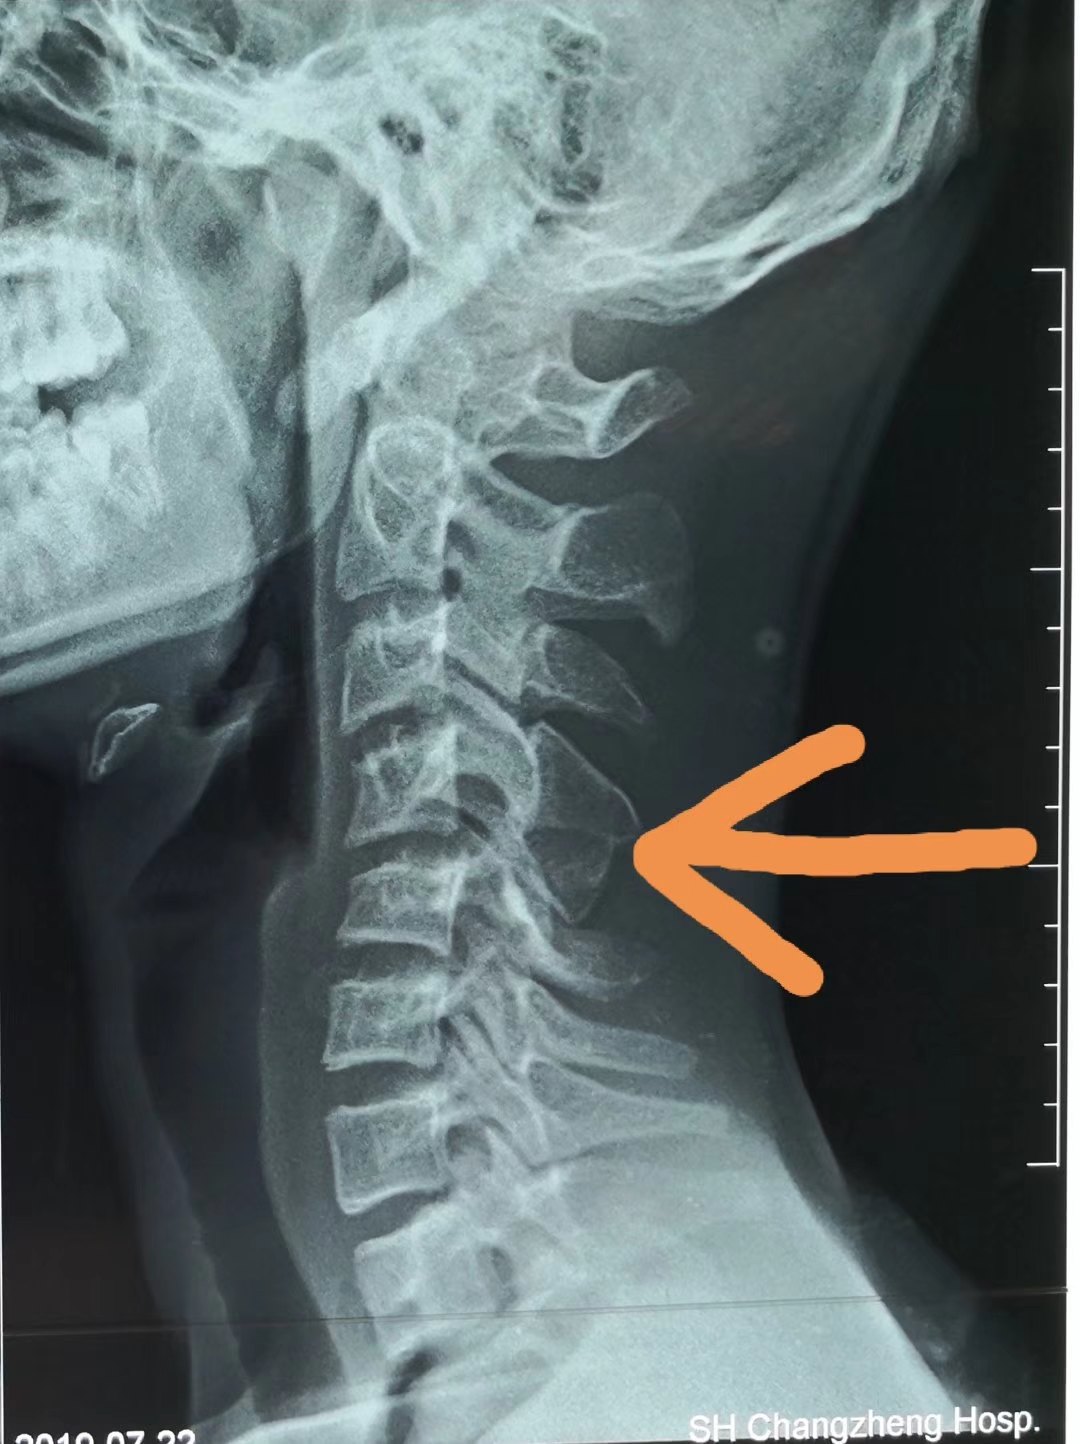

· 颈椎曲度反弓只是提示局部地方有退变,需要根据具体的症状做相应的处理。 如果是伴随颈部的地方疼痛和僵硬,可以选择按摩和热敷;另外就是可以选择药物比如替扎尼定,还可以选择一些膏药比如消痛贴膏有助于缓解。 如果是伴随上肢的麻木等不舒服,那么还可能是压迫了神经根,最好是完善颈部的磁共振检查,可以更为准确的判断病情。 平时要注意个人 · 知道颈椎反弓的成因,接着对因下药。 如果已经颈椎反弓了,可以适当地做一些牵引治疗。 如果病情较轻,通常采用坐位牵引,除此之外,还可以使用卧位牵引,可以在专业人士的指导下适当地借助一些工具,牵引的过程中,要注重牵引的强度,角度,时间以及重量。1510 · 颈椎反弓 一种常见颈椎病。颈椎有正常的生理弯曲,如果没有生理弯曲,甚至向相反的方向弯曲,称为反弓。 人类属于高级脊椎动物,颈椎"c"形向前的生理弧线保证了颈椎活动的高度灵活性,但人们常常发生违背颈椎生理曲线的姿态和活动。

1915 · 第一,颈椎反弓是一种普遍颈椎病。 颈椎骨有一切正常的生理弯曲,要是没有生理弯曲,乃至向反过来的方位弯折,称之为反弓。 颈椎反弓是组成颈椎病最常见的病理基本,而不适度用枕是造成 颈椎反弓的关键原因。 第二,颈椎反弓的严重后果: 颈椎反弓会造成许多 病症。 最先是颈椎骨主动脉受力,会造成大脑供血不足,次之是神经受力,造成神经根占位1 问: 颈椎反弓有什么后果,要怎么办 答: 颈椎反弓是会造成全身性的不正常的疾病。对人的危害极大。颈椎生理曲度变直或者颈椎生理曲反弓而造成颈椎管狭窄,挤压了脊髓而出现呕吐,眩晕,易昏撅摔倒而发生危险。脊髓病例一: 病情描述 颈椎曲度反弓如何解决颈椎曲度反弓如何解决 问题回答 病情分析:你好,预防颈椎病主要是减缓颈椎间盘退变的进程不良睡眠体位,工作姿势不当,不适当的体育锻炼都是颈椎骨关节退变的常见原因指导

· 得了颈椎反弓,怎么办 5 我才23岁啊,拍片子医生说是颈椎反弓,但是也没有怎么说治疗方法,就是平常多注意运动脖子,有条件做下牵引和按摩。 但我最近又感到恶心,头痛,怎么办啊?0800 · 李国民:颈椎生理曲度反弓怎么治疗? 你好,我是肩颈腰专家李国民。每天写一篇文章,分享我的实际治疗经验和案例,希望给你些启发和帮助,这是第7篇原创文章。 一、你的片子是否提示颈椎生理曲度反弓 今天清早的时候,有位朋友私信我,说他是颈椎生理曲度反弓,问我怎么治疗? 一2500 · 李国民:颈椎第5、6节反弓有什么办法? 做对治疗,远离瘫痪!你好,我是肩颈腰专家李国民。每天写一篇文章,分享我的实际治疗经验和案例,希望给你些启发和帮助,这是第844篇原创文章。 一、你颈椎反弓的原因是什么? 昨天有位朋友,她说他是颈椎第5、6节反弓,而且经常头晕,没办法